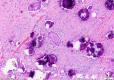

Fig. 4

Microscopic examination (Hematoxylin and eosin staining × 40) of Psammoma body formation.